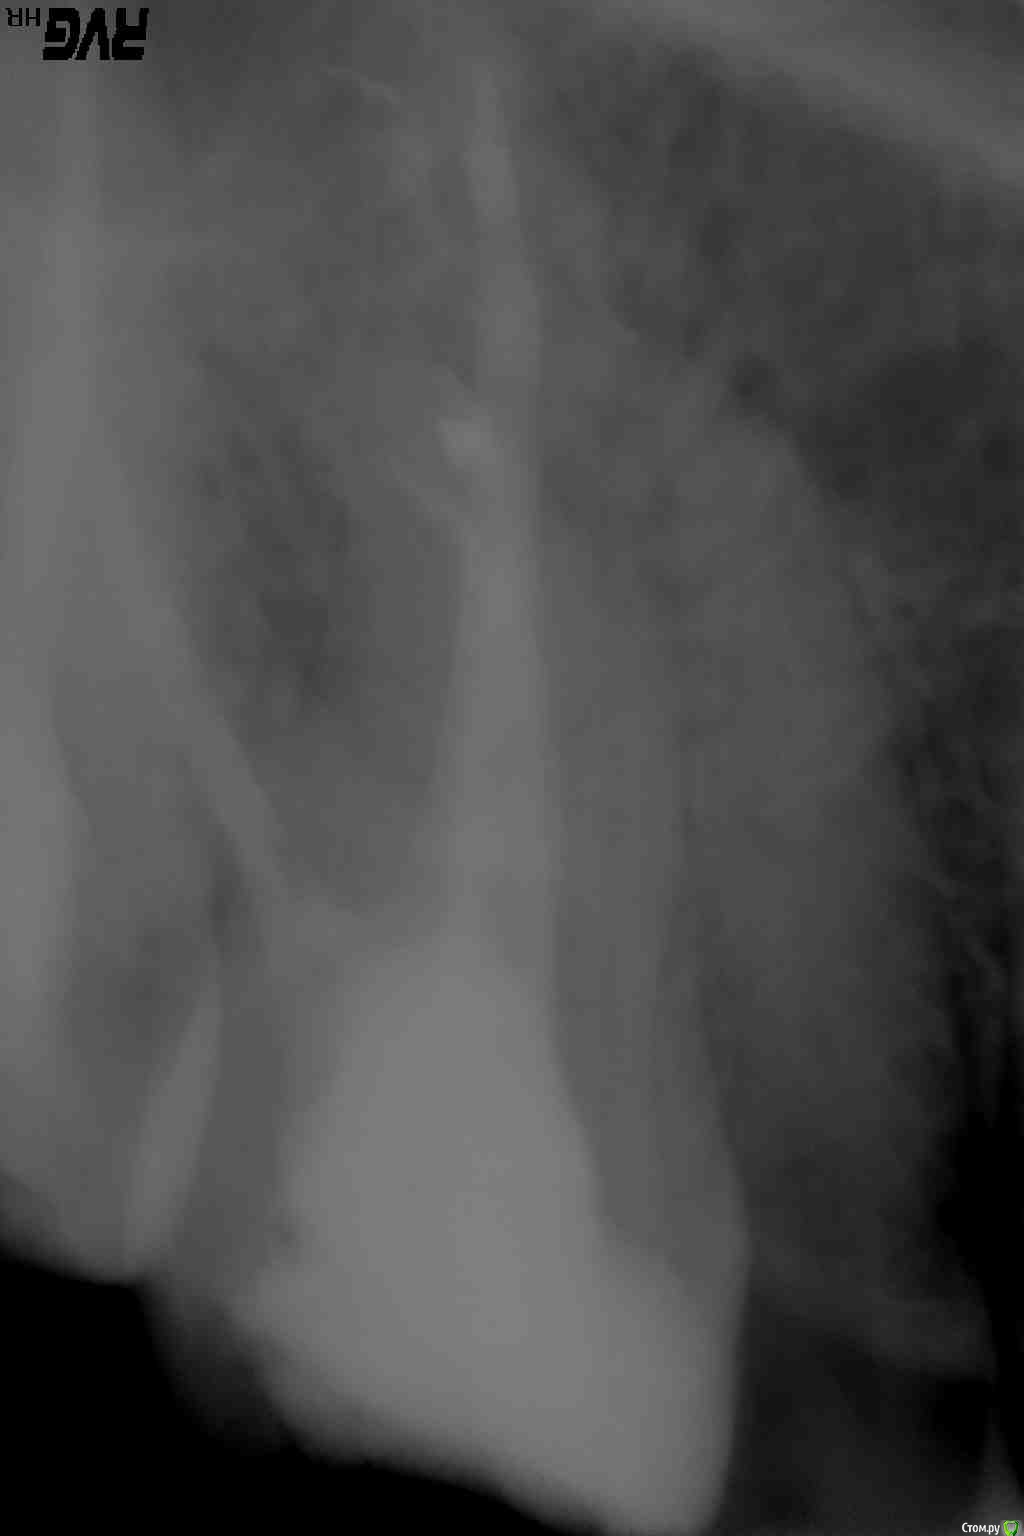

bozz903 Опубликовано 19 марта, 2016 Автор Поделиться Опубликовано 19 марта, 2016 Здравствуйте. С наступлением весны все тот же 16 зуб стал реагировать на температуру очень сильно. Также ноет сам по себе периодически. Боль не похожа на гиперчувствительность эмали.Сделал новые снимки. Что нибудь можно сказать по сравнение с теми, которые прикреплены в первом моем сообщении? Ссылка на комментарий

DmitrySH Опубликовано 19 марта, 2016 Поделиться Опубликовано 19 марта, 2016 (изменено) Низкая информативность снимков. Даже на ОПТГ качество лучше Изменено 19 марта, 2016 пользователем DmitrySH Ссылка на комментарий